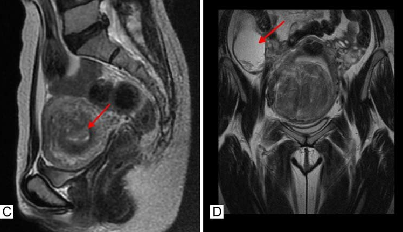

She has vast experience in operating on several patients with huge fibroids. She has performed the most challenging surgeries with utmost precision and safety. She has operated on massive abdominal mass lesions including a 4kg Fibroid uterus. Her experience in performing laparoscopic hysterectomy with confidence and expertise needs to be mentioned.